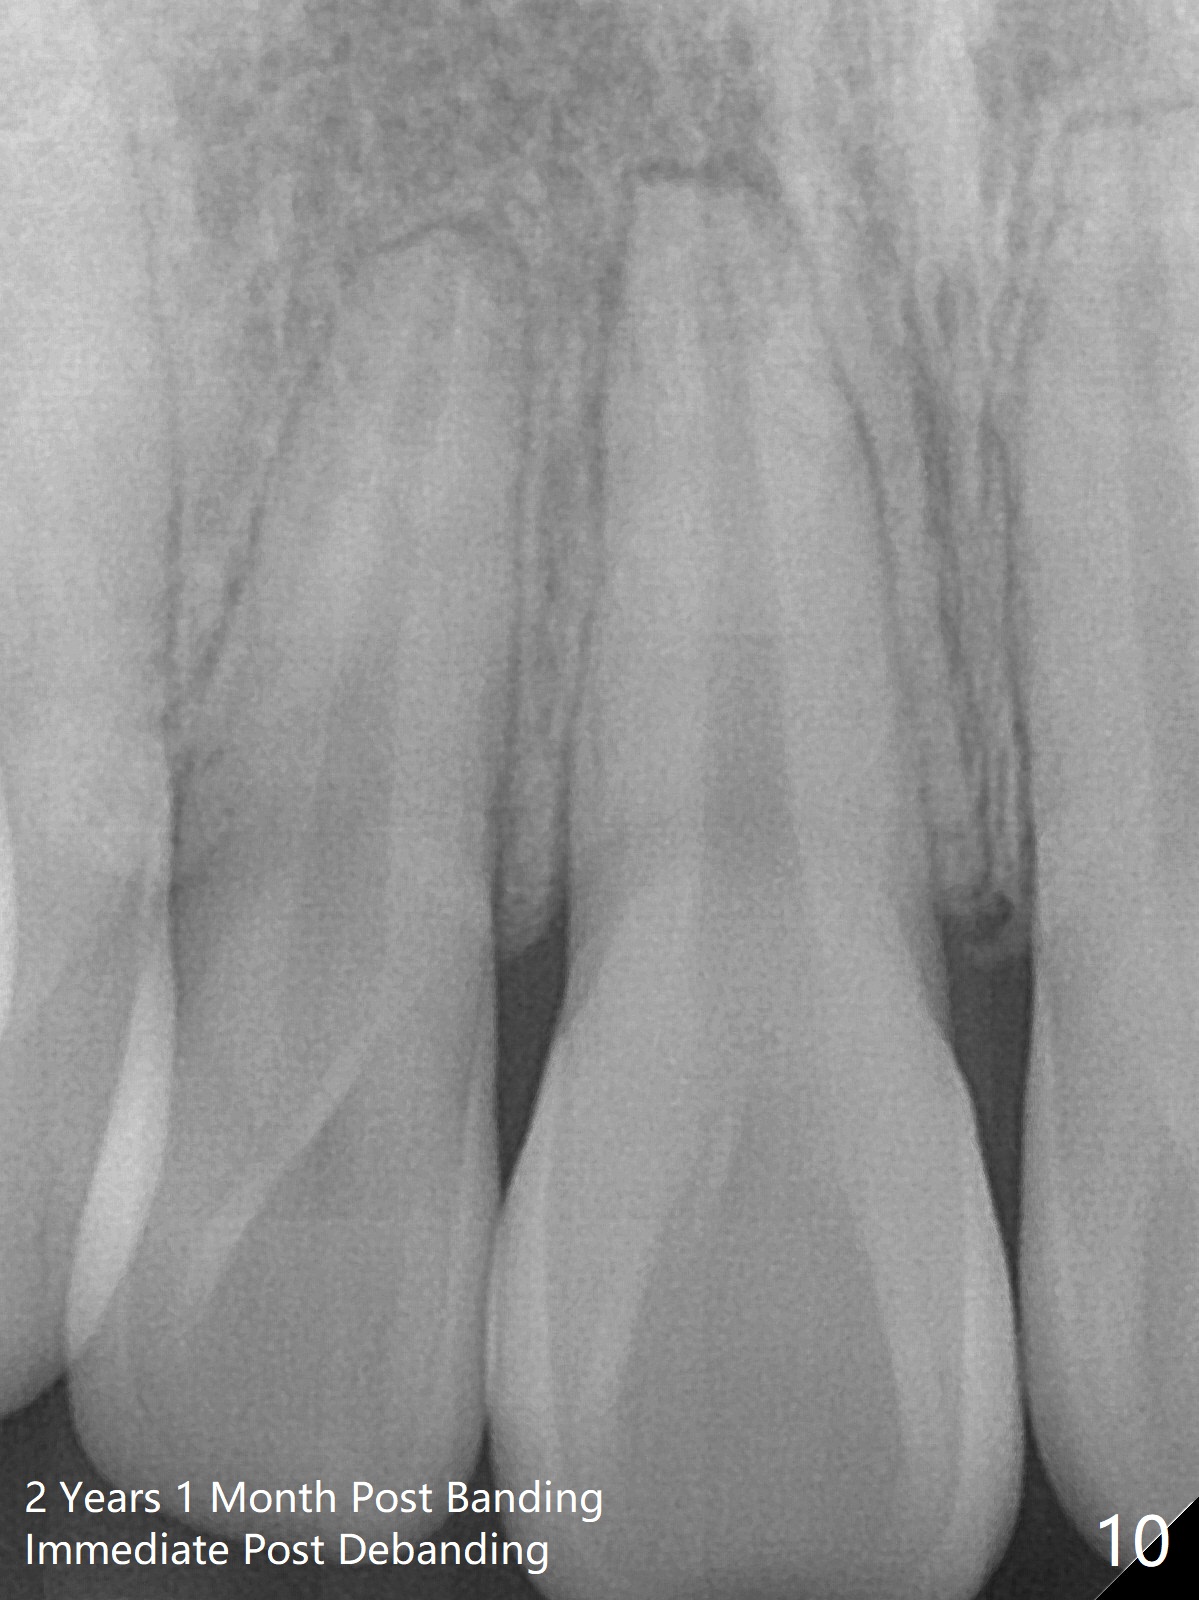

Four days post extraction of 4 of the 1st bicuspids, the patient returns for bracketing. It appears easier to place molar bands post extraction than without extraction. Spaces are larger. Anterior open bite (Fig.1-3) is due to premature contact of the mesiobuccal cusp of UR7 and the buccal tube at LR 7. To facilitate LR3 distalization, power chains are placed between LR3 and 6 (Fig.1 .014 niti wires), while tension in LL seems to be too high for power chains (Fig.3). The lower wire dislodges from the 2nd molar bands twice in 2 weeks; it appears that LR3 has been distalized (Fig.4); to reduce the chance of wire displacement, power chains x 5 are to be placed in LL 3-7 as well.

Plans: Next visit, do not necessarily change the lower wire so that it is easier to engage the wire to L2s' brackets once spaces arise. Use full arch power chains when L3s complete distalization.